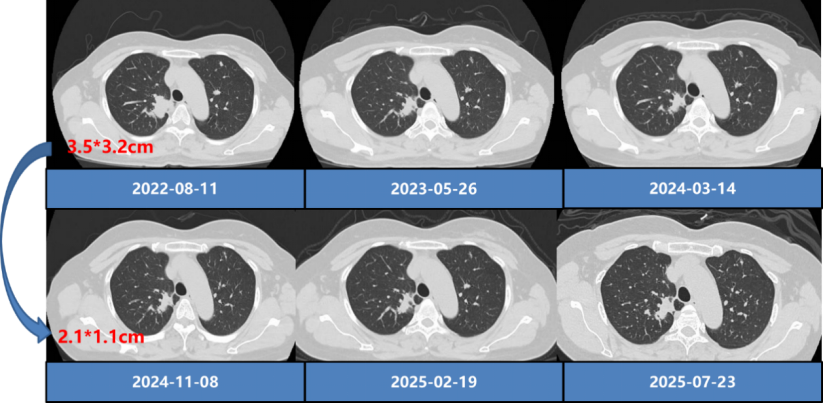

2022年7月至今,行长春瑞滨+重组人血管内皮抑制素+三代EGFR-TKI(奥希替尼/阿美替尼/伏美替尼)治疗。治疗期间多次复查,其中,2022年10月复查,右上肺肿块较前缩小,脑转移灶消失,CEA水平明显下降。2024年11月复查,右上肺肿块较基线缩小,骨转移灶消失。具体数据及疗效评估如下图:

影像学结果:

充分考虑口服长春瑞滨的确切疗效、良好安全性、便捷性及节拍化疗、抗血管生成、EGFR-TKI的协同作用,本患者二线接受“长春瑞滨+重组人血管内皮抑制素+三代EGFR-TKI”治疗。治疗3个月后复查,原发病灶明显缩小,疗效评估达到PR;脑转移灶及骨转移灶先后实现CR,并持续维持。该案例初步证实,口服长春瑞滨双靶联合策略不仅可克服EGFR-TKIs耐药,且安全可控、实施便捷,为临床破解 EGFR突变晚期NSCLC的“后 TKI时代”困局,提供了切实可行且极具潜力的治疗新范式。